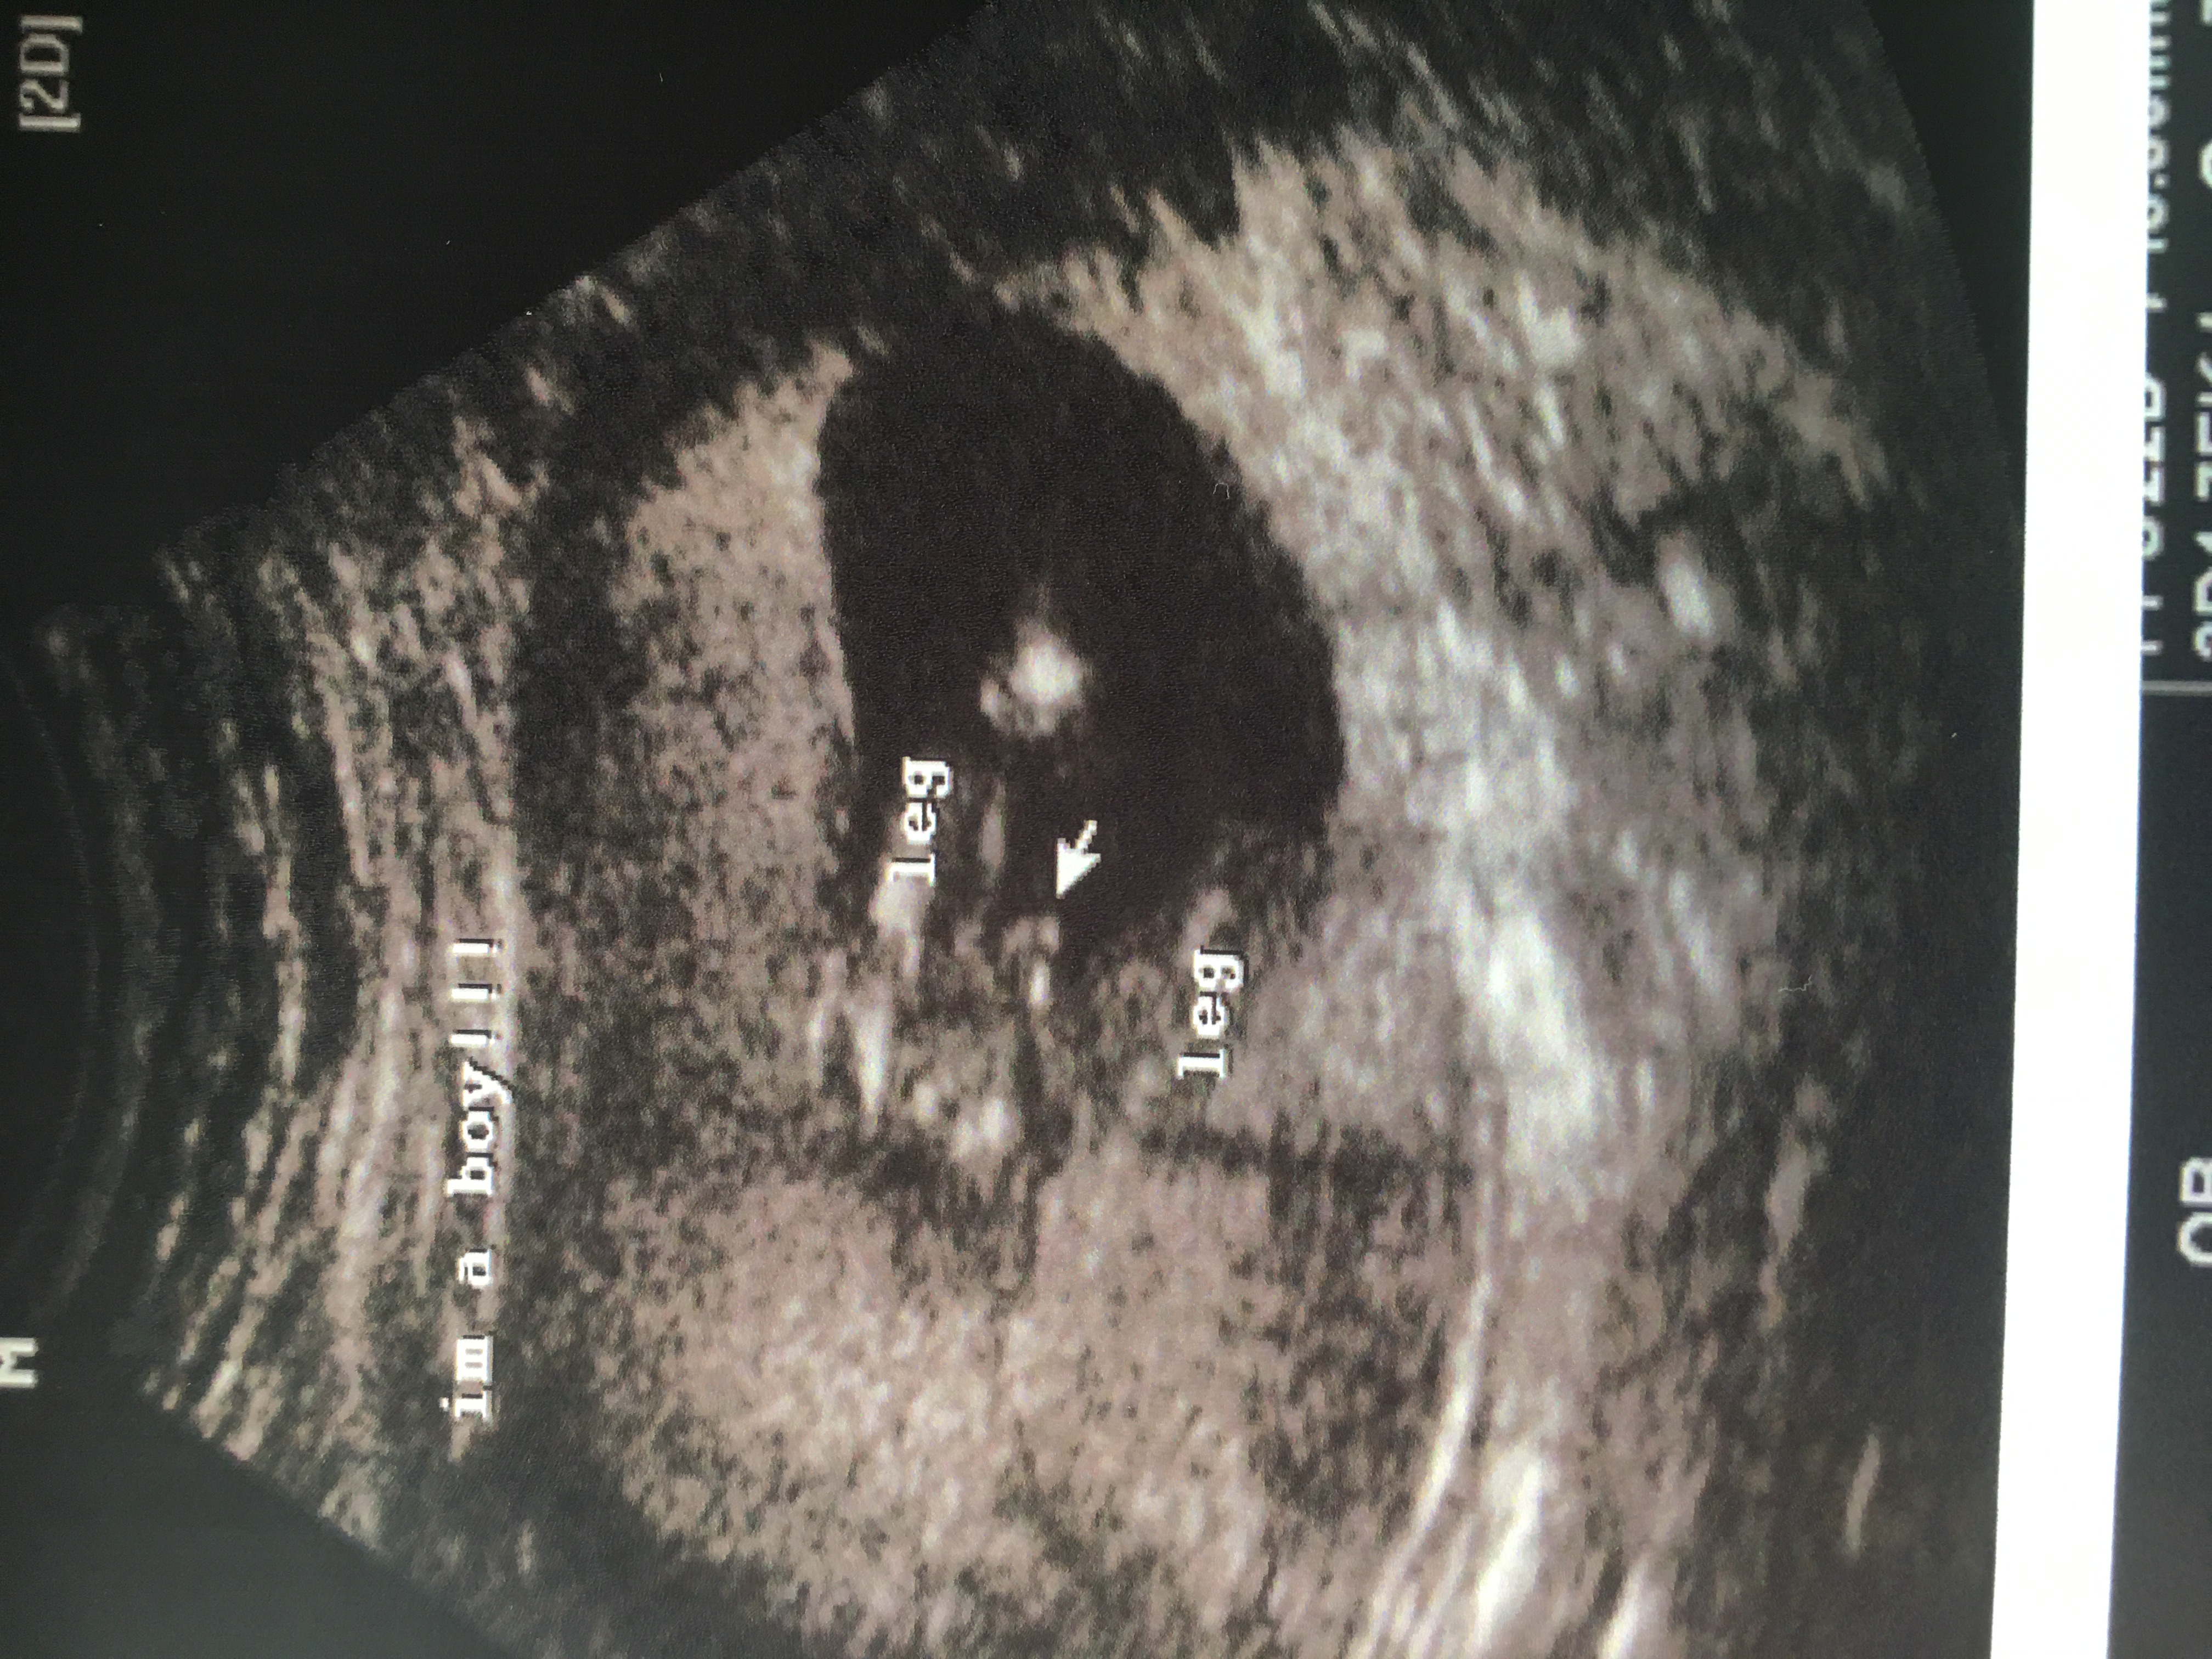

100% BOY!!!!! ALL BOY!!!! I'm so excited... thank you lovely ladies for all the love you showed me on this site!!

Ladies can you please help! Dr said babies legs are closed. THANK YOU in advanceAttachment 33406

possible stacking in pic 3. leaning boy but quality is pretty poor so could easily be pink still :)

They aren't brilliant pics but I think I can see stacking in second picture which would indicate boy... At 13 weeks there's a possibility you could see boy but girl parts can still look swollen too...x